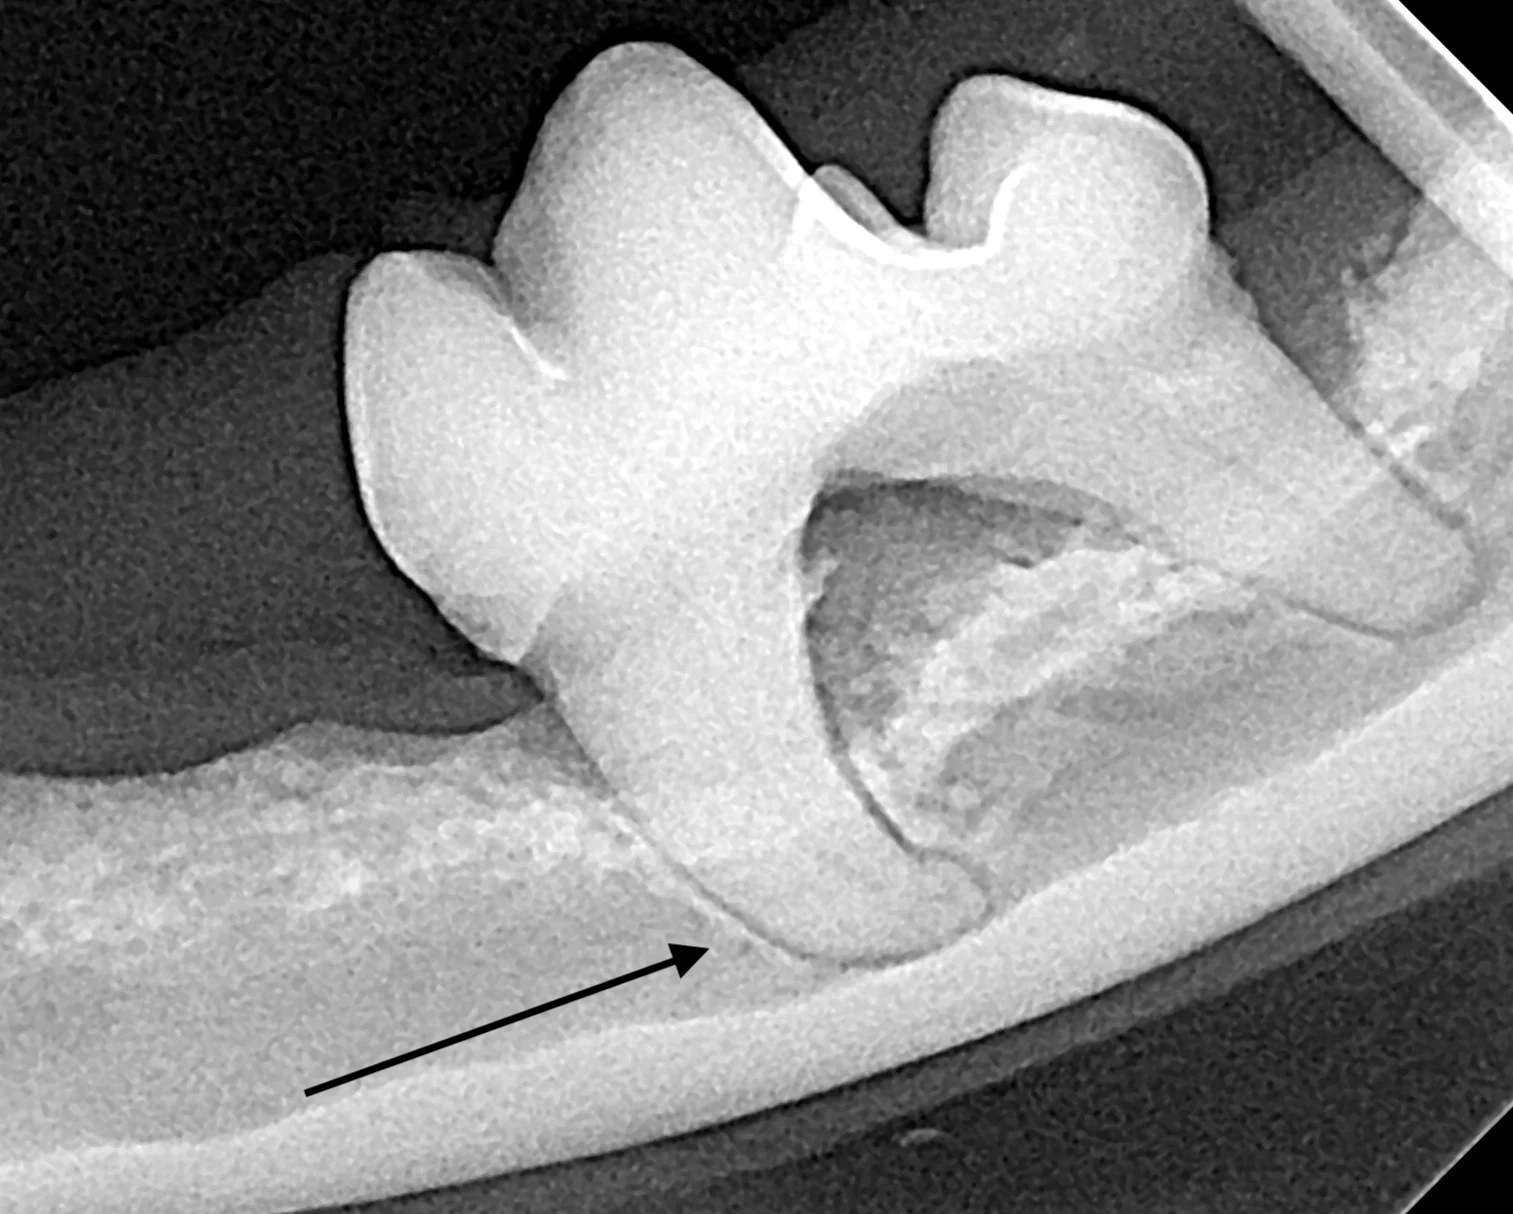

Root ankylosis, root resorption, root dilaceration (ie, curvature), and/or bulbous roots can increase the difficulty of a tooth extraction (Figure 12). Tooth roots occasionally break during extraction attempts. Diseased tooth roots should typically not be left in place due to the potential for pain and infection.5 Safe root extraction includes removal of additional alveolar bone or widening of the alveolus with a high-speed bur to create a moat around the remaining root fragment prior to lifting it out (see Suggested Reading).5

Root ankylosis (A), root resorption (B), bulbous root (C; arrow), and root dilaceration (ie, curvature) (D; arrow) are tooth root anomalies that can increase the difficulty of tooth extraction.

Root tips may be easily displaced into the mandibular canal or the nasal passage and maxillary sinus. Displacement is more likely with significant oral disease or bone loss around the root apex. Roots displaced into abnormal locations should be removed surgically by a board-certified veterinary dentist.